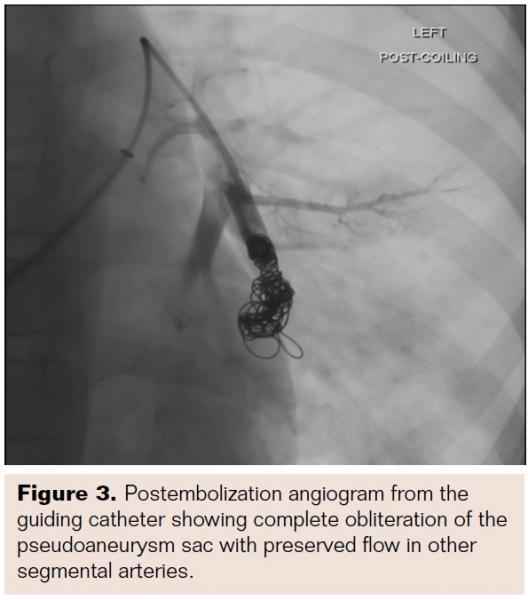

The pigtail catheter was exchanged for a 4 Fr Infiniti cobra catheter (Cordis Corporation) over the stiff glide wire. Using the 4 Fr cobra catheter as a guiding catheter, the segmental left lower lobe pulmonary artery branch was selectively catheterized using a hydrophilic 3 Fr Progreat microcatheter (Terumo). The microcatheter was placed within the sac of the aneurysm and multiple 0.018˝ platinum coils (Hilal embolization micro-coils; Cook Medical) with sizes ranging from 6 mm to 10 mm were deployed to fill the sac and the proximal feeding artery. After completion of the procedure, check angiograms were performed with the microcatheter and guiding catheter, which showed complete occlusion of the pseudoaneurysm and its feeding artery with preserved flow in the other segmental arteries (Figure 3).